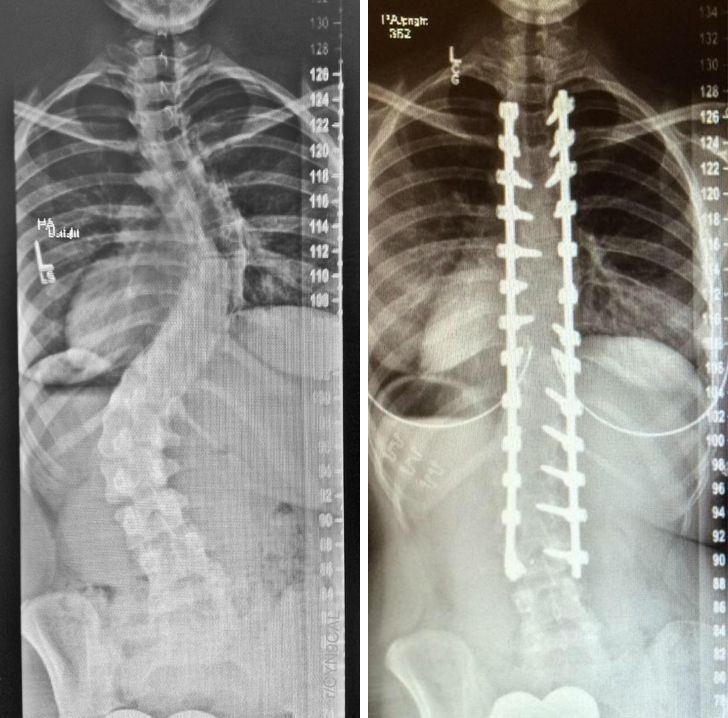

7. عکس اشعه ایکس قبل و بعد عمل جراحی فیوژن ستون فقرات